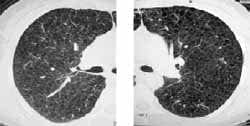

Como parte del seguimiento de su enfermedad, le fueron practicadas en nuestro hospital Radiografía, TAC de tórax y se realizó una revisión de la patología. La radiografía de tórax evidenció opacidades reticulares finas en ambos pulmones (Figura 1).

| Figura 1. Radiografía PA de tórax. Opacidades reticulares finas. Figura | Figura 2. TAC de alta resolución. Lesiones quísticas, de pared fina, comprometiendo el parénquima pulmonar en forma difusa. |

La radiografía de tórax, se caracteriza por la presencia de opacidades reticulares finas de predominio basal (por sumatoria de imágenes de las lesiones quísticas). Ocasionalmente pueden definirse imágenes quísticas en el parénquima.

Clásicamente el volumen pulmonar está aumentado. Se han descrito líneas septales y edema intersticial en relación con obstrucción de linfáticos. El 49% de los pacientes pueden presentar neumotórax y el 13% derrame pleural quiloso (9). El compromiso pleural a repetición puede causar engrosamiento de extensión variable.